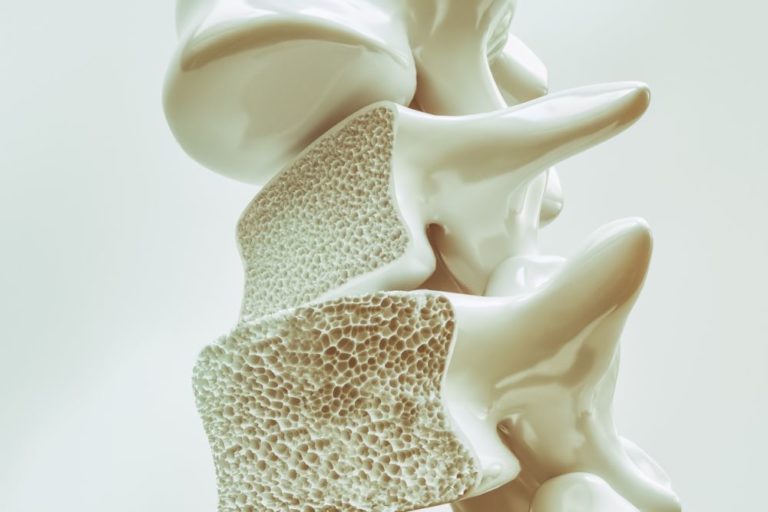

Pacienti s osteoporózou by se neměli bát pravidelně cvičit

Miliony lidí s osteoporózou by se neměly bát pravidelně cvičit, uvedli odborníci v pokynech zaměřených na posílení zdraví kostí, snížení rizika pádů a zlepšení držení těla. Tento stav, který oslabuje kosti a zvyšuje pravděpodobnost jejich zlomení, postihuje více než 150 milionů osob na celém světě. Mezi nejčastější úrazy patří zlomenina zápěstí, kyčelních a páteřních kostí. […]

Osteoporóza přichází nenápadně

Denzitometrie neboli měření hustoty minerálů v kostech je jedním z nejúčinnějších způsobů prevence osteoporózy. Ta může v pokročilém stádiu způsobovat ošklivé zlomeniny dokonce i při lehkém nárazu nebo kýchnutí. Nemoc postihuje takřka každou třetí ženu po menopauze, nevyhýbá se ale ani mužům. Kostní denzitometrie umí riziko osteoporózy včas odhalit a umožňuje zvolit vhodný způsob léčby. […]

Když se lámou kosti

Mírný pád, lehký náraz nebo pouhé kýchnutí. Situace, které mohou skončit zlomeninou, a překvapivě tak odhalit nemoc, která se nenápadně vyvíjí celá léta. Kosti člověka trpícího osteoporózou jsou křehké, snadněji se lámou, a právě fraktura bývá často prvním příznakem tohoto onemocnění. Vyskytuje se u každé třetí ženy a jednoho z pěti mužů nad padesát let. […]